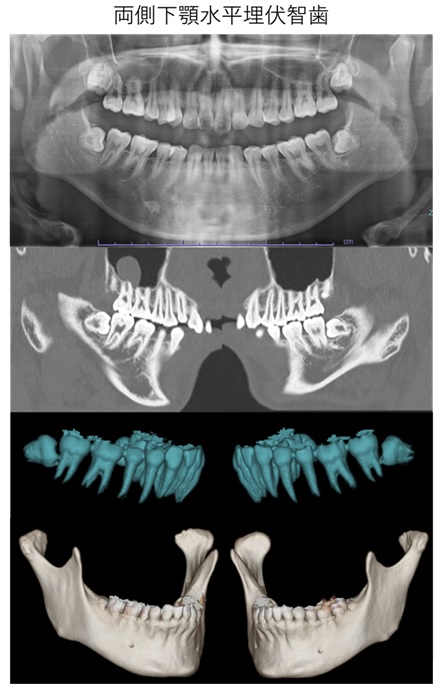

埋伏歯の抜歯

埋伏歯とは、歯茎や顎の骨の中に埋まって出てこない歯のことを指します。特に親知らず(第三大臼歯)が埋伏することが多く、通常17歳から25歳頃に生えてくる最後の歯です。多くの場合、親知らずは正しい位置に生えず、周囲の歯や歯茎に問題を引き起こすことがあります。

抜歯は、局所麻酔を用いて痛みを感じないように行います。埋伏歯の抜歯が複雑である場合や、患者さんが不安を感じる場合には全身麻酔を使用します。